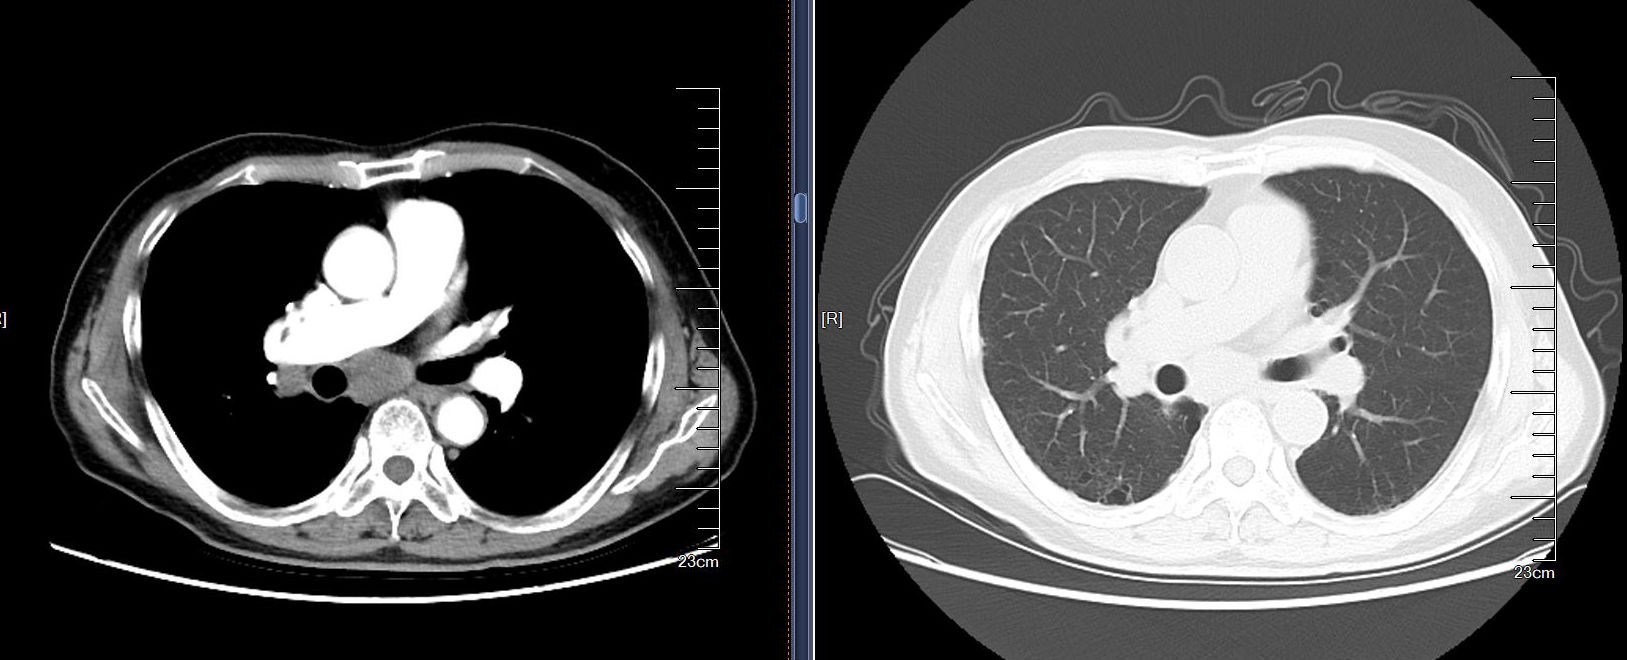

患者为一名67岁老年男性,因“咳嗽、咳痰、胸痛1月”入院,2个月前因“急性心肌梗死”于院内行“冠脉药物涂层支架植入术+冠脉球囊扩张成形术”,术后心绞痛、心律失常等病情仍不稳定,持续抗血小板改善冠脉供血治疗。入院后胸部CT提示肺门及纵隔区淋巴结肿大,临床高度怀疑肿瘤转移性(图1)。患者及家属对诊断的精准度要求极高,急需安全、高效的诊断技术,明确病理类型以启动后续治疗。

图1:患者胸部CT提示纵隔淋巴结多发异常肿大